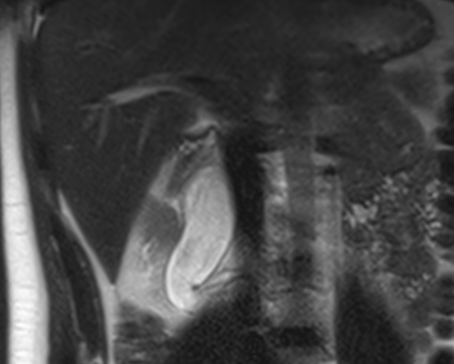

In diesem Fallbericht beschreiben wir einen 17-jährigen Patienten, der mit rez. ausgeprägten Koliken in unserer Abteilung vorstellig wurde. Initial erfolgte bei Hydronephrose °III und pos. Steinanamnese des Vaters eine CT-Abdomen nativ, welche bereits den V.a. einen retrocavalen Harnleiter rechts ergab. Eine Szintigraphie bestätigte eine urodynamisch relevante Obstruktion bei ausgeglichener Nierenfunktions. Bei Symptomatik erfolgte eine retrograde Ureteropyelographie mit JJ-Einlage. Im weiteren Verlauf wurde noch eine MRT-Angiographie durchgeführt, welche den Befund eindeutig bestätigte. Daraufhin erfolgte am 10.11.2025 die daVinci-assistierte Ureterureterostomie rechts in Linksseitenlage. Hierfür wurden 4 Arbeitstrokare und ein Kameratrokar verwendet. Die Gesamtoperationszeit lag bei 181 min, die reine Konsolenzeit bei ca. 100 min. Intraoperativ erfolgte ein JJ-Wechsel. Die Anastomose erfolgte mit einer 4.0 Quill-Naht in fortlaufender Technik. Der Blutverlust lag bei ca. 20 ml. Postoperativ waren die Schmerzen mit Novalgin gut beherrschbar. Die Entlassung erfolgte am 5. postoperativen Tag nach DK-Entfernung.

Abbildung 1 [Abb. 1], Abbildung 2 [Abb. 2], Abbildung 3 [Abb. 3], Abbildung 4 [Abb. 4], Abbildung 5 [Abb. 5], Abbildung 6 [Abb. 6], Abbildung 7 [Abb. 7], Abbildung 8 [Abb. 8], Abbildung 9 [Abb. 9], Abbildung 10 [Abb. 10]